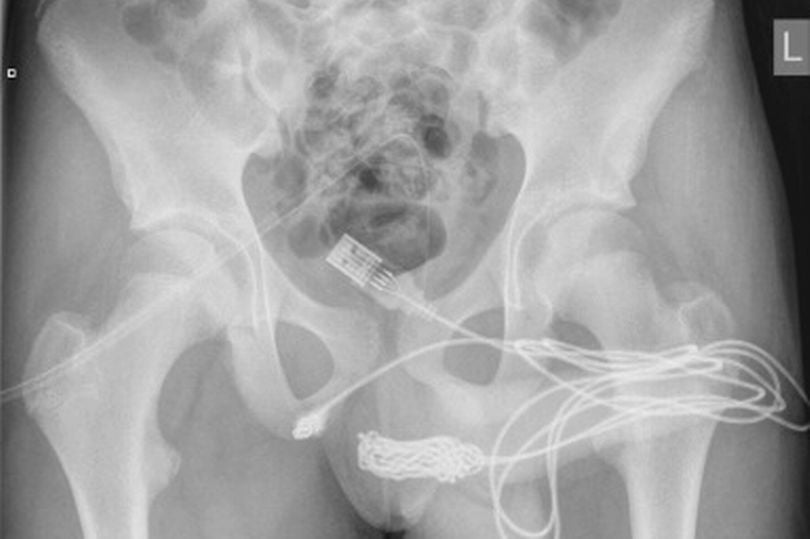

Die Ärzte waren ob des Vorgehens des Jungen schockiert. Ein Teenager beschloss nämlich, ein USB-Kabel in seinen Penis zu schieben, um sein Inneres zu vermessen, ein schmerzhaftes Unterfangen. Kurz nachdem er das Kabel einführte wurde ihm schnell klar, dass dies eine schlechte Idee war. Der junge Engländer bekam schnell Schmerzen, zudem ließ sich das Kabel nicht mehr entfernen.

Zu allem Übel verhedderte und verknotete sich das Kabel auch noch. Die Ärzte schrieben: "Es wurde festgestellt, dass die beiden distalen Anschlüsse des USB-Kabels aus dem äußeren Harnröhrengang herausragen, während der mittlere Teil des verknoteten Kabels in der Harnröhre verblieb. Der Patient war ein ansonsten fitter und gesunder Jugendlicher ohne psychische Störungen in der Vorgeschichte."

Im Gespräch mit der Mutter stellte sich heraus, dass der Junge das Kabel als Mittel für "sexuelle Experimente" benutzt hatte. Die Ärzte mussten schlussendlich den Bereich zwischen den Genitalien und dem Anus aufschneiden, um das Kabel zu entfernen.